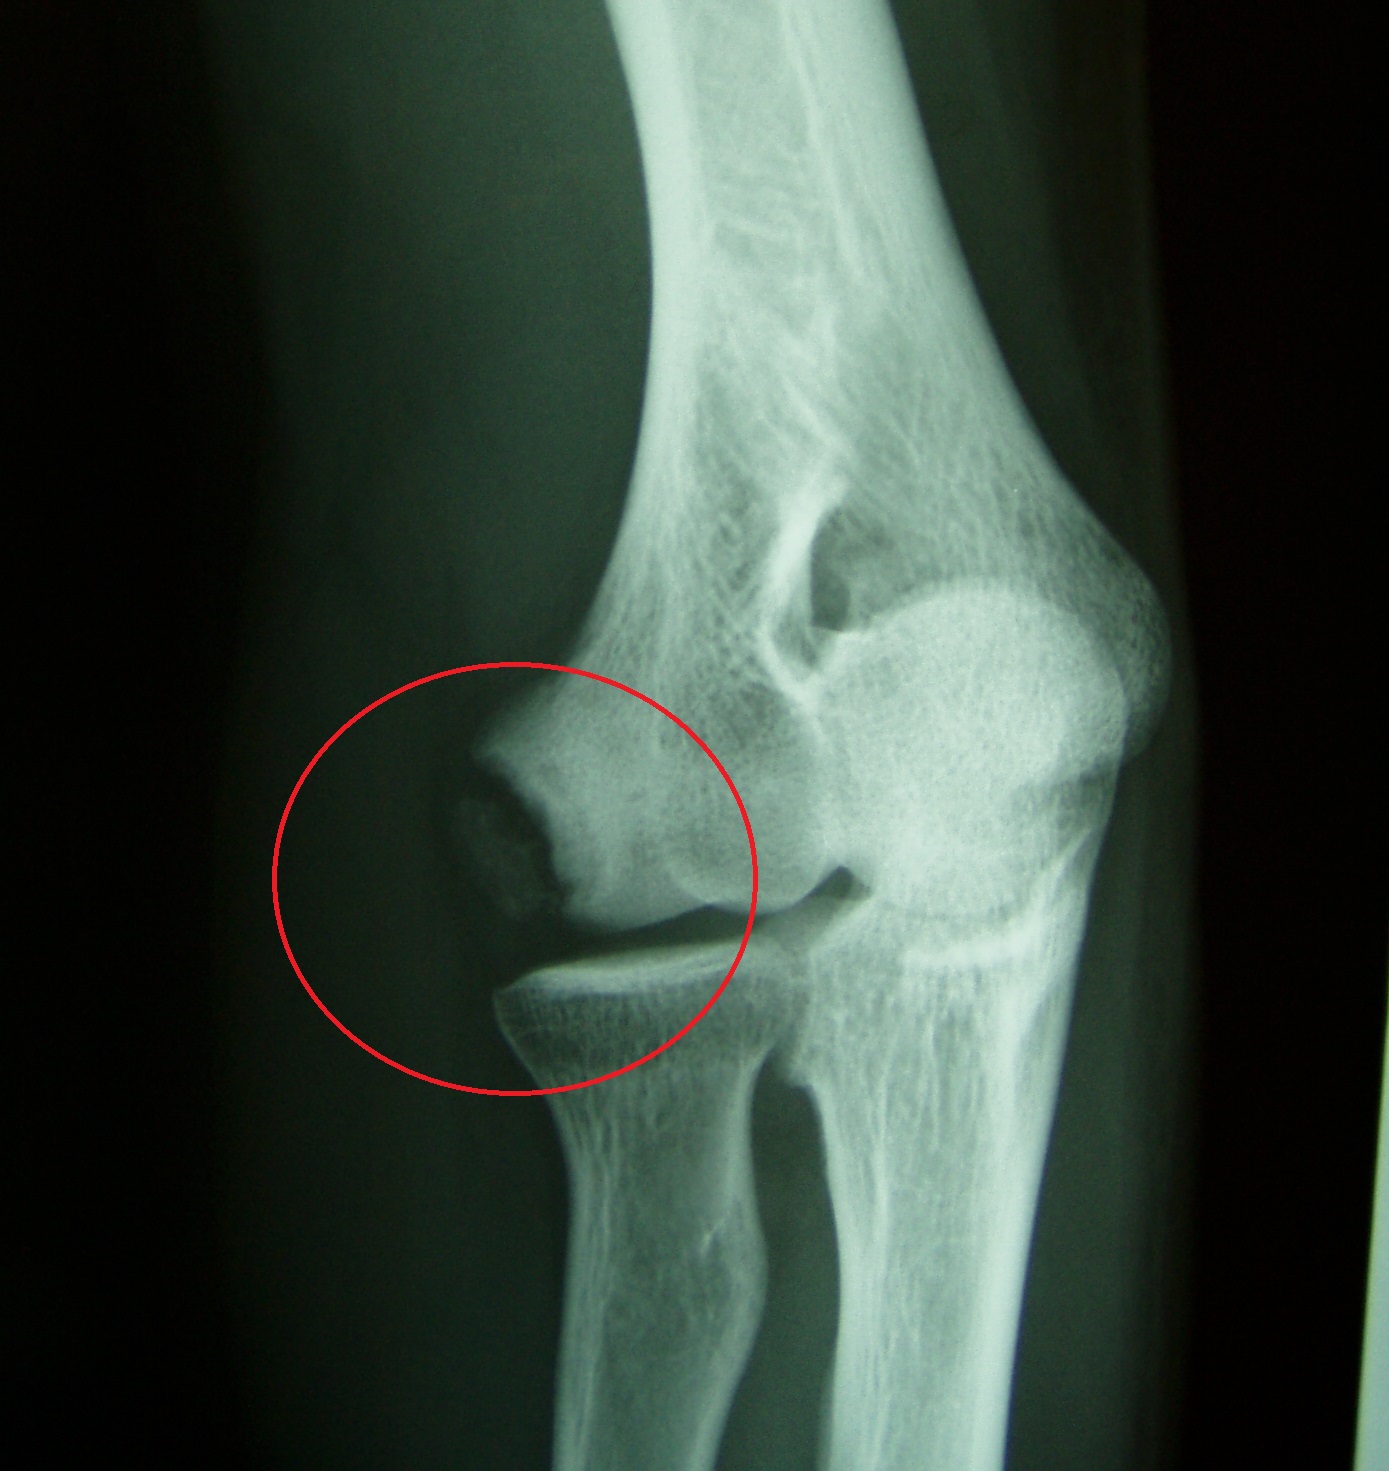

야구 엘보는 야구 투구, 특히 성장하는 투수에서 발생하는 과도한 사용으로 인해 발생하는 스포츠 장애로, 주로 내측 (그림 1), 외측 (사진 1)의 던지는 팔꿈치에 던지는 통증이 특징입니다. , 팔꿈치 머리 (사진 2). 증상은 종종 점차적으로 나타나고 만성화되므로 팔꿈치 통증에 주의를 기울여야 합니다. 던지는 동작의 가속 단계 (가속)는 팔꿈치 굴곡, 외반 및 팔뚝 외전에서 발생합니다. 내측 형에서는 내측 굴근에 의해 팔꿈치 안쪽을 던지면서 내 측근, 내측 측부 인대, 척골 신경을 잡아 당겨 팔꿈치 내부의 미세 손상을 일으킵니다. 심한 경우 상완골의 내측 상과는 견인으로 인해 찢어짐 골절이 발생합니다. 측면 형에서는 상완골의 팔꿈치 측면의 반경에 압력이 가해져 골괴사, 결손 및 느슨한 신체와 함께 골 연골염 해부 증이 발생합니다. 후방 유형은 감속 (추적) 동안 팔꿈치 확장 위치에 있고 견인력이 척골의 주두에 적용되어 찰과상 및 스트레스 골절과 같은 변화를 초래합니다.

사진 1 측면 유형 : 상완골의 머리 뼈에 있는 자유로운 뼈

이러한 증상은 X- 레이에서 뼈의 변화를 동반 할 수 있습니다. 내측 유형에서는 상완골 내측 상과의 골 비후, 골단 선 분리 및 내전근 영역의 자유 뼈가 관찰됩니다. 측면 유형에서 뼈 변형, 결함 및 상완골 및 반경의 머리의 자유 뼈 조각이 관찰됩니다. 후방 유형에서는 척골 주두의 열구 골절 및 스트레스 골절이 관찰됩니다.